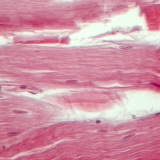

400 дахин томруулсан

Биологи